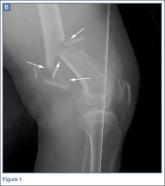

ArticleEmergency ImagingAuthor:Calvin Sy,mdPublish date: September 1, 2015 A 45-year-old man presented with severe left leg pain and deformity after being struck by a car while driving his moped. Read More